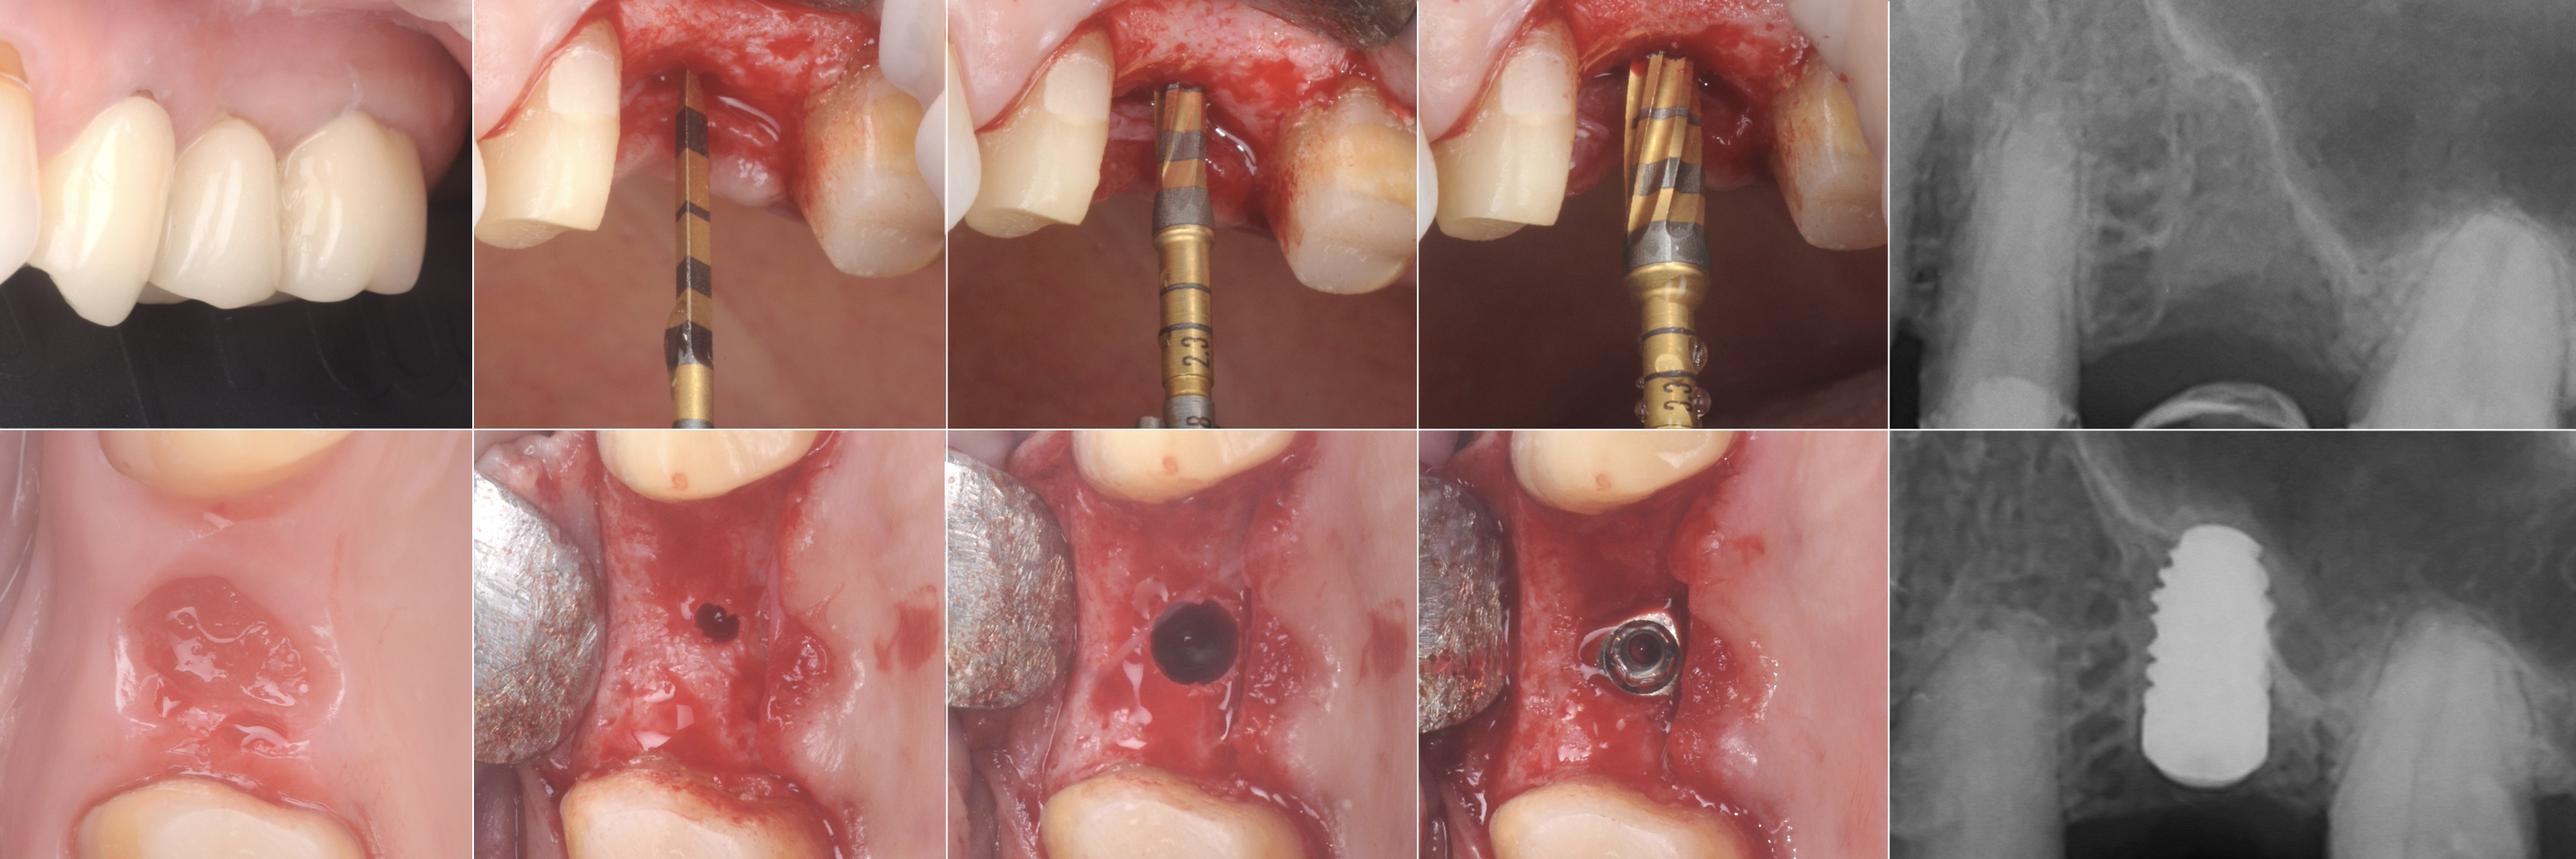

Nel presente caso clinico eseguito dal Dott. Tommaso Ghedini viene esemplificato l’utilizzo delle frese Versah per la osseodensificazione e la gestione del rialzo del seno mascellare per via transcrestale.

Nello specifico la paziente necessitava di una riabilitazione implantare in sede 25. L’osso residuo era sufficiente dal punto di vista orizzontale per il posizionamento di un impianto di diametro standard, come si può osservare dalla foto in visione occlusale, mentre vi era un deficit nell’altezza ossea residua.

L’analisi radiografica tridimensionale, fondamentale per escludere patologie sinusali in atto, e bidimensionale mostrano una morfologia del pavimento del seno mascellare che renderebbe complessa una manovra di rialzo tramite osteotomi secondo la tecnica di Summers.

Pertanto, l’utilizzo delle frese Versah in senso antiorario sotto abbondante irrigazione con un movimento di rimbalzo-pompaggio ha permesso l’espansione ossea non solo in senso apicale ma anche in senso trasversale come si può osservare dalla radiografia di controllo.

La sequenza di preparazione ha creato un’osteotomia che potesse accogliere l’impianto con un torque adeguato ma senza stressare la componente trabecolare.

La gestione semplificata del caso è stata quindi resa possibile grazie alla specifica azione osseodensificante delle frese Versah, minimizzando il trauma per il paziente.